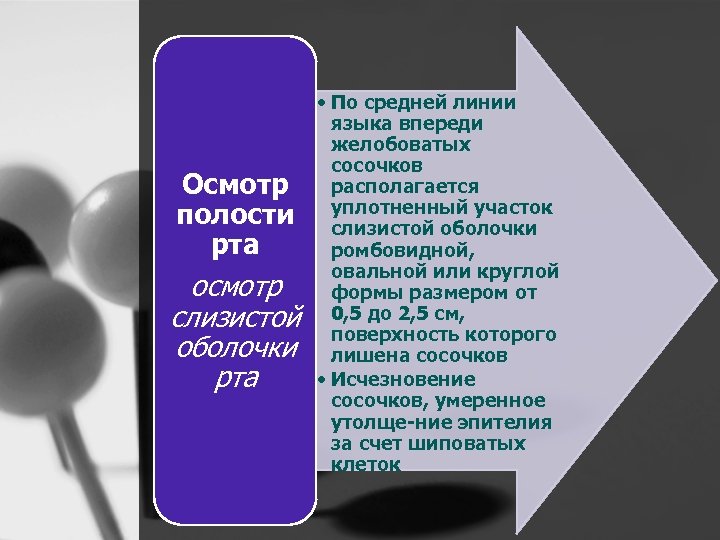

Осмотр полости рта осмотр слизистой оболочки рта • По средней линии языка впереди желобоватых сосочков располагается уплотненный участок слизистой оболочки ромбовидной, овальной или круглой формы размером от 0, 5 до 2, 5 см, поверхность которого лишена сосочков • Исчезновение сосочков, умеренное утолще ние эпителия за счет шиповатых клеток